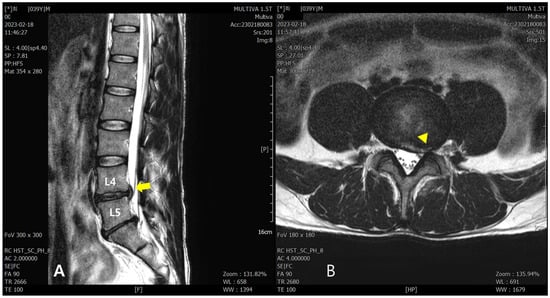

On lumbar spine T2-weighted turbo-spin-echo MRI conducted on 18 February 2023, disc extrusion from the central to left foraminal zone at the L4–L5 spinal segment was observed with a high signal intensity in the annular fissure. Additionally, the left L4 and proximal left L5 nerve roots were closely abutted against the extruded disc (Figure 1).

Figure 1. Lumbar spine MRI conducted on 18 February 2023. (A) T2-weighted turbo-spin-echo sagittal view: the arrow indicates the area of the extruded L4/5 disc, and the L5 nerve roots are abutted against the extruded disc. (B) T2-weighted turbo-spin-echo axial view: the triangle indicates the area where the disc has extruded from the central to left foraminal zone.